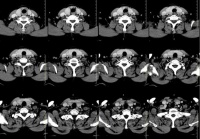

双侧甲状腺肿大 - CT病例